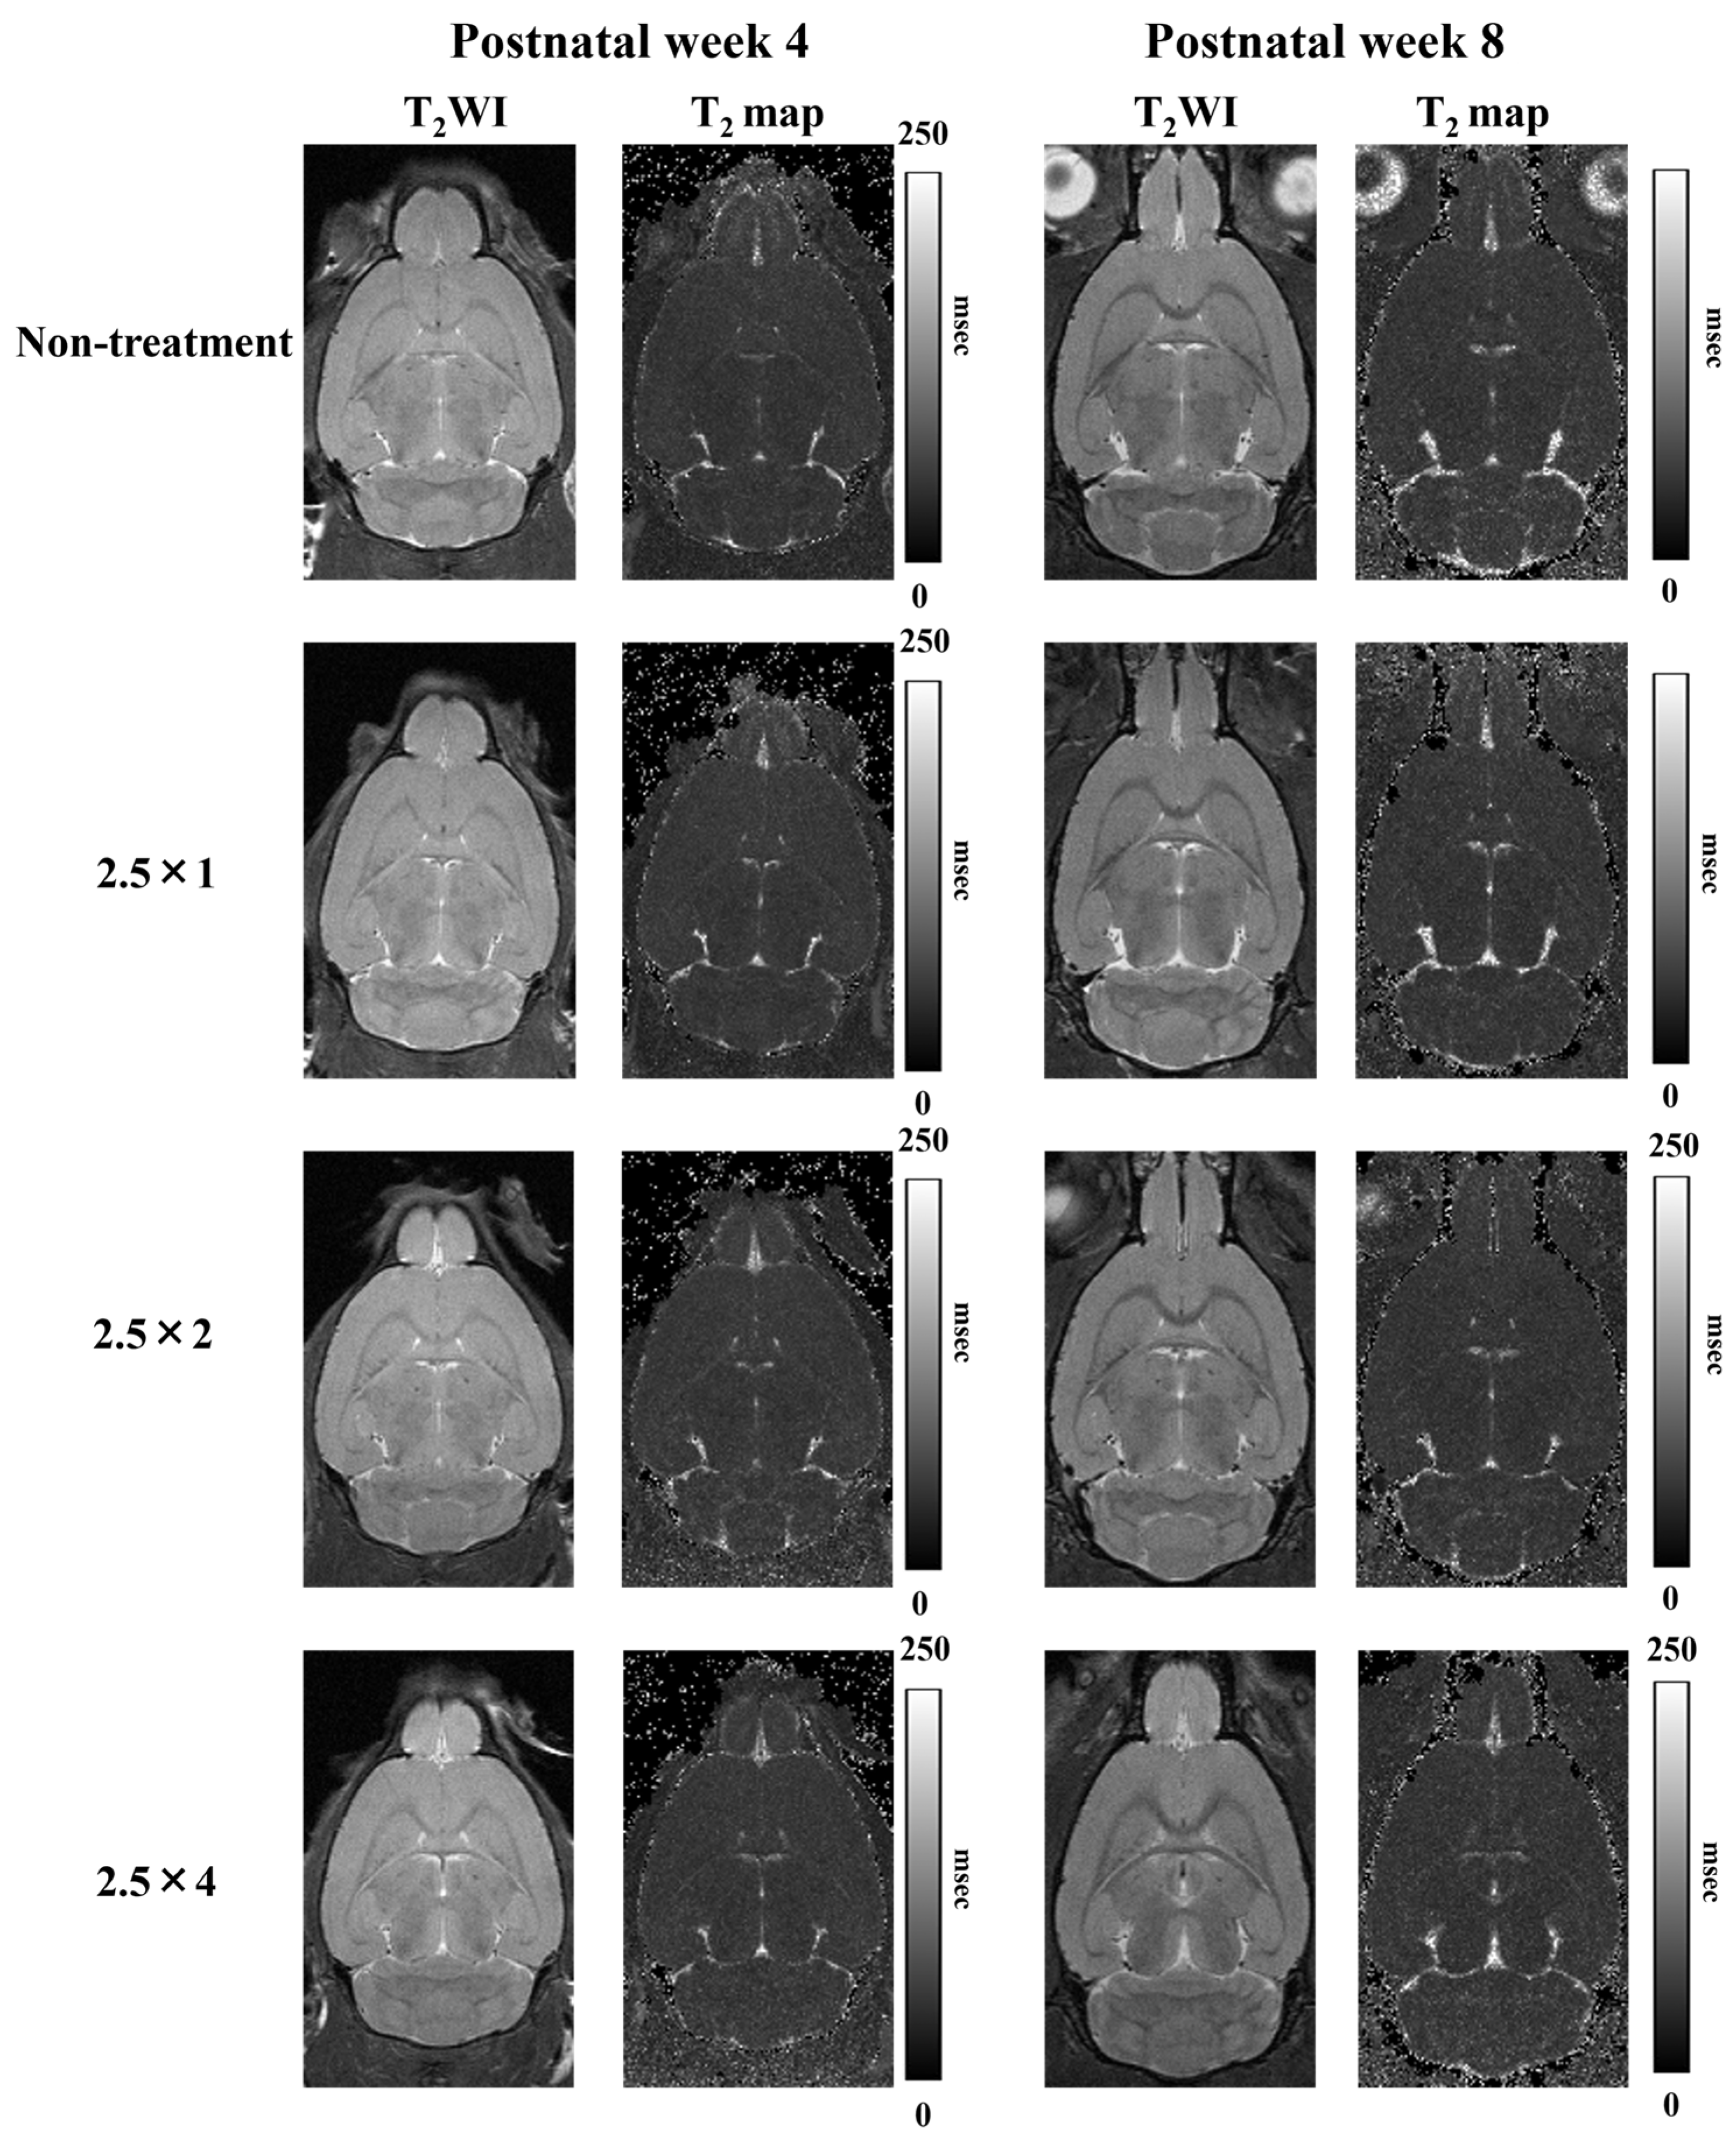

3.3. T2 Relaxation Time